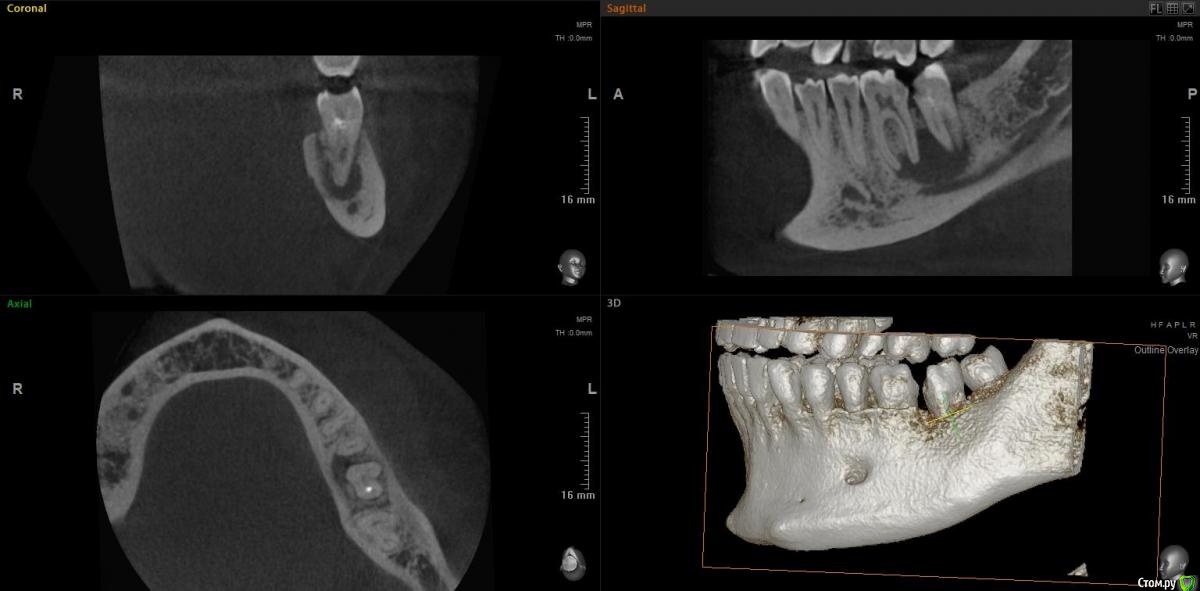

jm3300 Опубликовано 15 ноября, 2020 Поделиться Опубликовано 15 ноября, 2020 Коллеги, можно в данном случае вытянуть консервативно? Ссылка на комментарий

Irouil Опубликовано 15 ноября, 2020 Поделиться Опубликовано 15 ноября, 2020 Тут, похоже, не(только) корневая киста, язычно карман. Вопрос в терапию, наверное, но я скажу - нет 1 Ссылка на комментарий

red_butler Опубликовано 15 ноября, 2020 Поделиться Опубликовано 15 ноября, 2020 Имхо нужно в терапию, по данным срезам не увидел проблем с реэндо 2 Ссылка на комментарий

jm3300 Опубликовано 15 ноября, 2020 Автор Поделиться Опубликовано 15 ноября, 2020 Тут, похоже, не(только) корневая киста, язычно карман. Вопрос в терапию, наверное, но я скажу - нетвозможный карман тоже смущает Ссылка на комментарий

Дмитрий М Опубликовано 15 ноября, 2020 Поделиться Опубликовано 15 ноября, 2020 самого пациента ещё не видел. попросили КТ посмотретьок )) тогда понятноесли только из снимков то 36 пробовать сохранять, эндо и наблюдение а вот 37 больше за удаление был подобный случай, только киста немного меньше была но так же с вовлечением корней 36 и 37 терапевт хотела удалить оба, но решили оставить 36 полечить и наблюдать, а 37(разрушен не подлежал восстановлению) удалил, кисту почистил, ч/з 3 мес имплант. в итоге с 36 все хорошо 1 Ссылка на комментарий